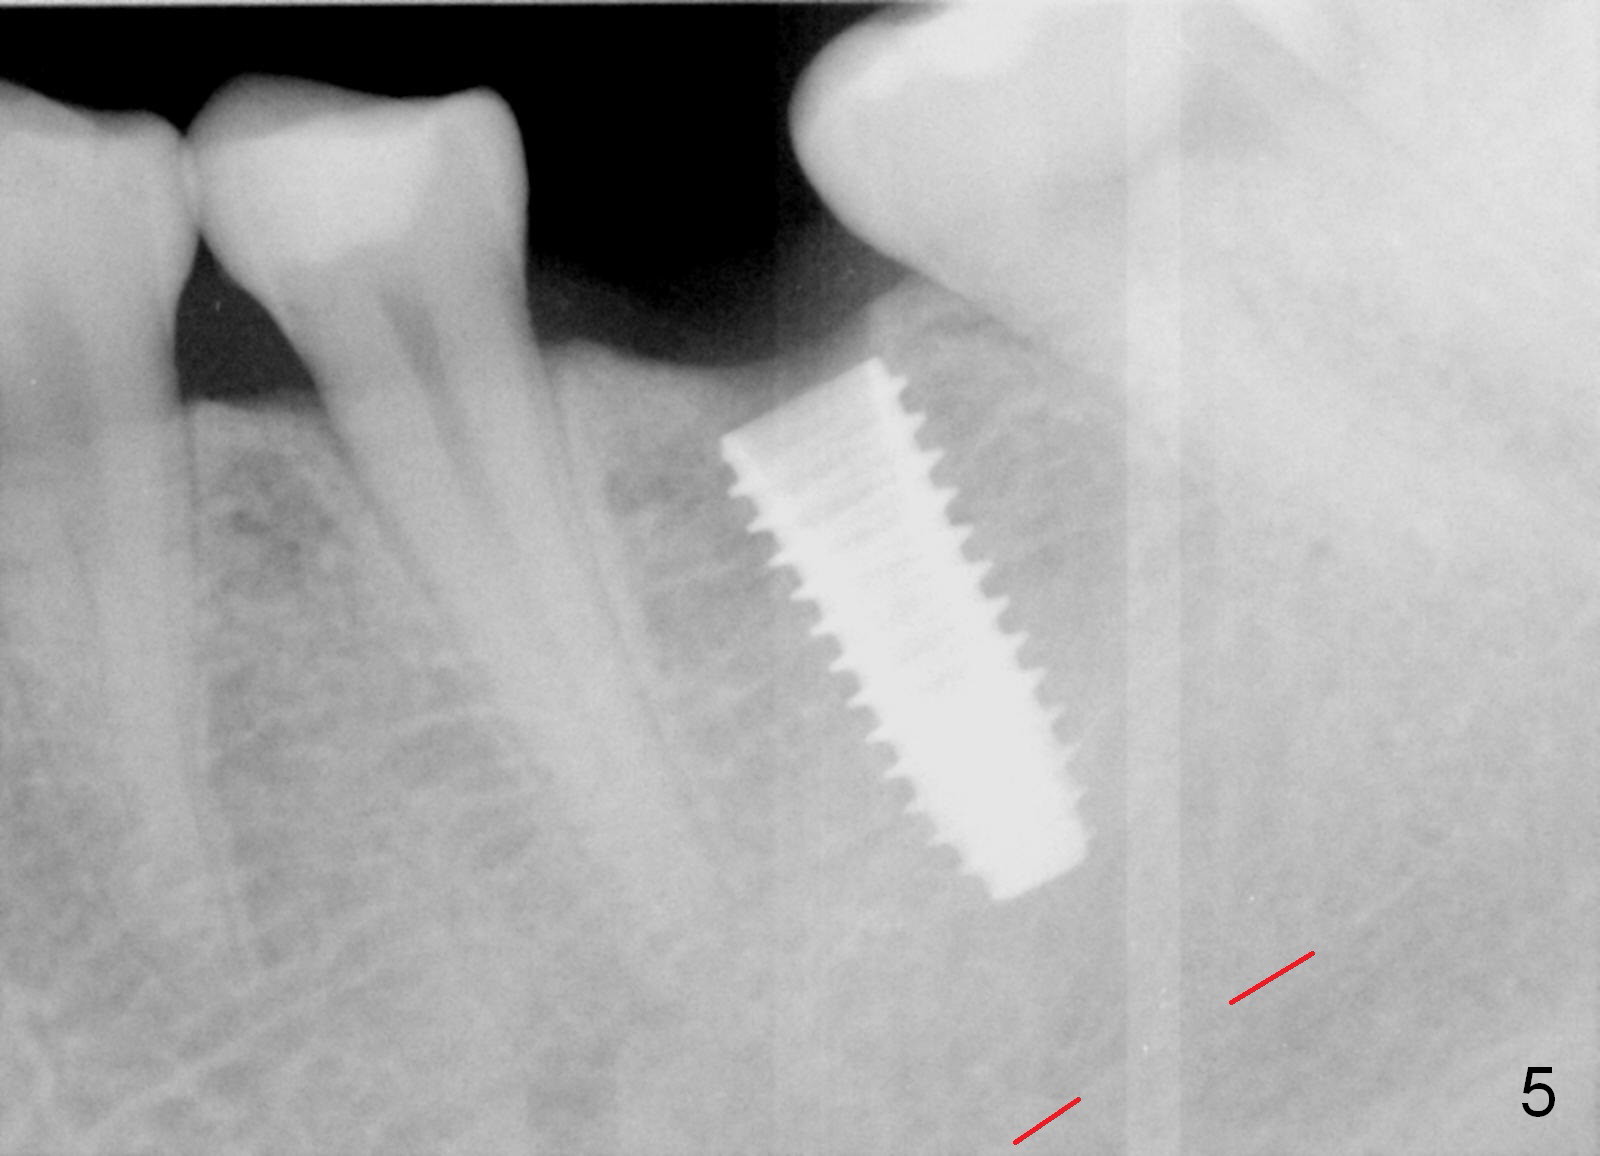

In fact, the buccolingual width of the ridge is sufficient to have a 4.5x11.5 mm implant placed (Fig.4,5, D3 bone, <35 Ncm). Proximal reduction is done before and after placement of a 5.5x4(3) mm abutment. Heavy abutment height adjustment is provided as well as the opposing prior to immediate provisional.